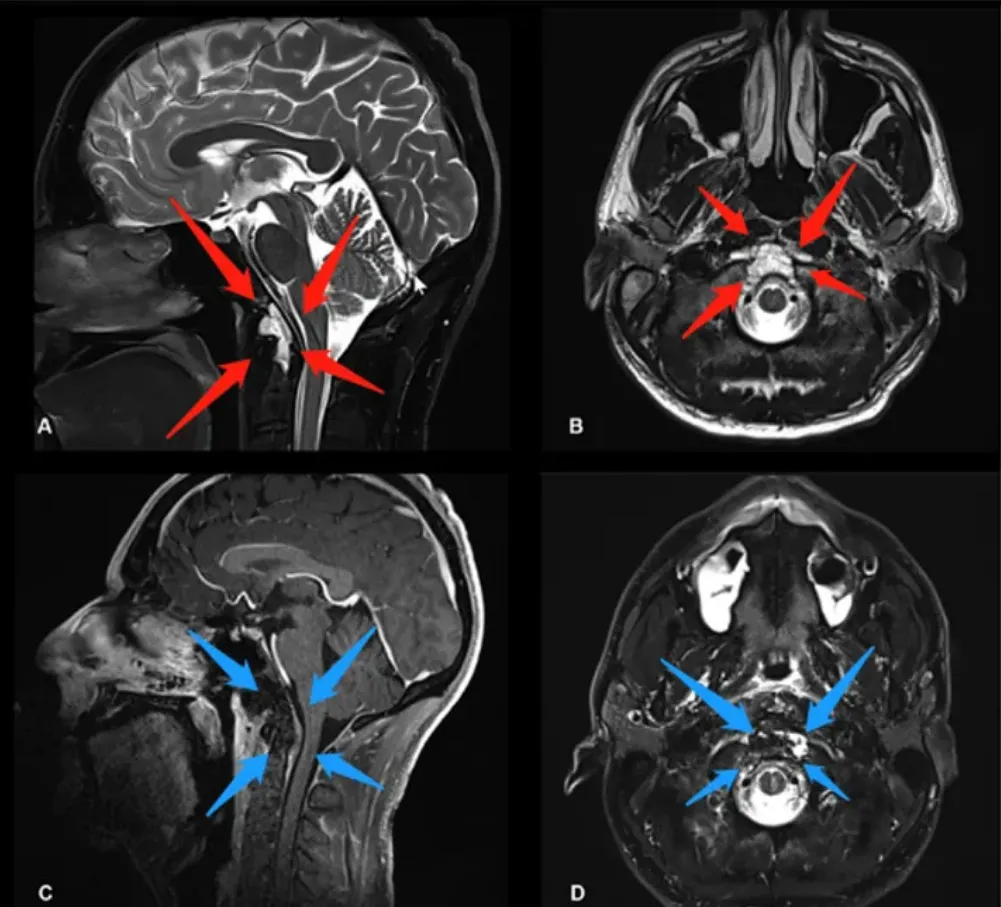

术前术后影像资料对比。术前(红色箭头):图A、B显示了下斜坡及齿状突可见中线占位病变,影像学表现为脊索瘤侧伸有限。术后(蓝色箭头):图C、D显示了用于闭合瘤腔的脂肪移植物,没有肿瘤残留。术后MRI显示完成了肿瘤全切除。术后患者无神经功能缺损。病理检查显示为典型脊索瘤。